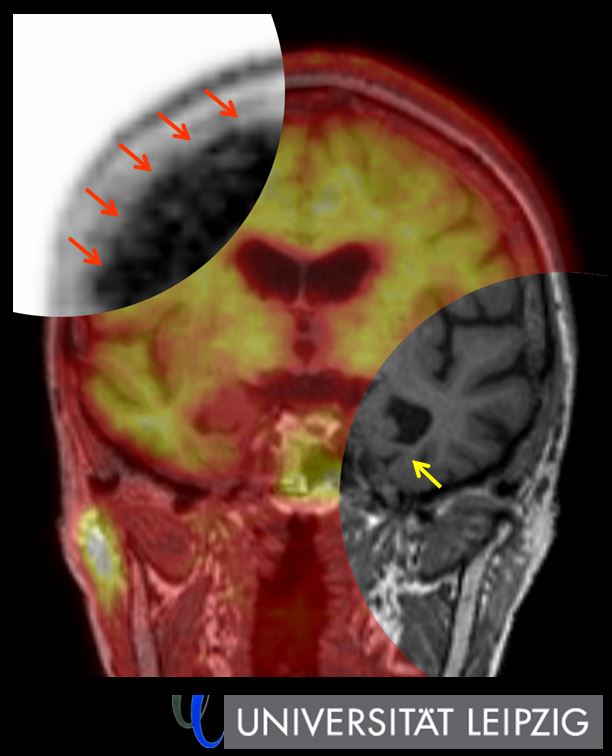

Bestrahlungserfolg bei Hirntumoren lässt sich mit kombinierter PET/MRT vorhersagen

Patienten mit Glioblastom, einer besonders aggressiven Variante von Hirntumoren, entwickeln oft sogenannte Rezidive – das bedeutet, der Tumor kehrt trotz der…

Röntgenkongress: Molekulare Bildgebung für bestmögliche Demenz-Abklärung

„Eine bildgebende Hirnuntersuchung gehört bei der Abklärung von Patienten mit Demenzerkrankungen zum Standard“, betont Prof. Dr. Henryk Barthel von der Klinik…